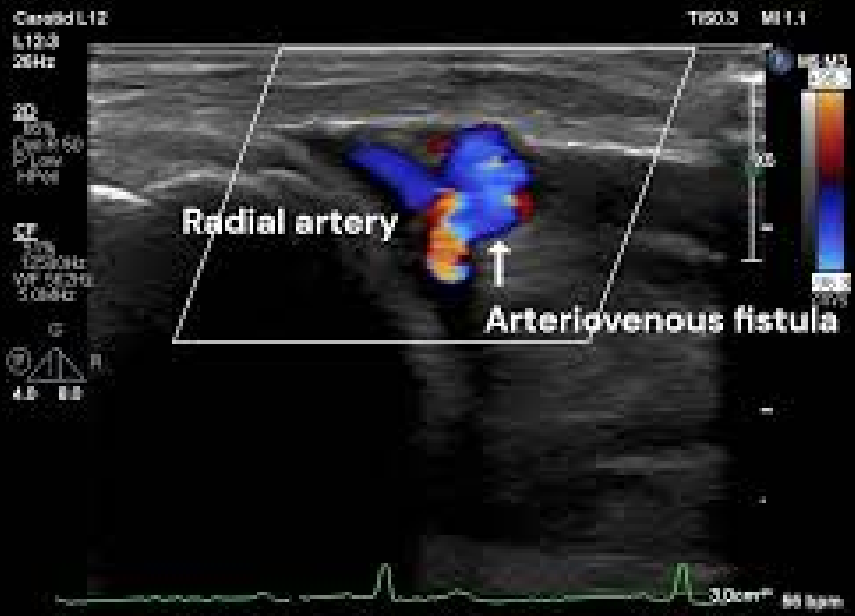

图1.dTRA形成动静脉瘘的照片、超声表现和血管造影图像。

(A)观察到扩张的头静脉。(B)箭头显示动静脉瘘的入口,即桡动脉与静脉连接处。浅表超声检查发现远端桡动脉有一个直径为2.0mm、流速为3.75m/s的动静脉瘘。(C)桡动脉造影。显示远端桡动脉与手背静脉网之间存在分流,并且头静脉和贵要静脉显影。分流位于桡动脉至靠近拇指掌骨的静脉处。(D)常见的远端桡动脉穿刺部位(三角形)和本例的穿刺部位(星形)。

然而,在本病例中,穿刺是在超声引导下进行的,位置更靠近远端,位于拇长伸肌腱与第二掌骨基底的交点附近(图1D)。据认为,AVF的形成是因为穿刺针在穿透手背静脉网后,再刺穿了桡动脉的浅掌支。